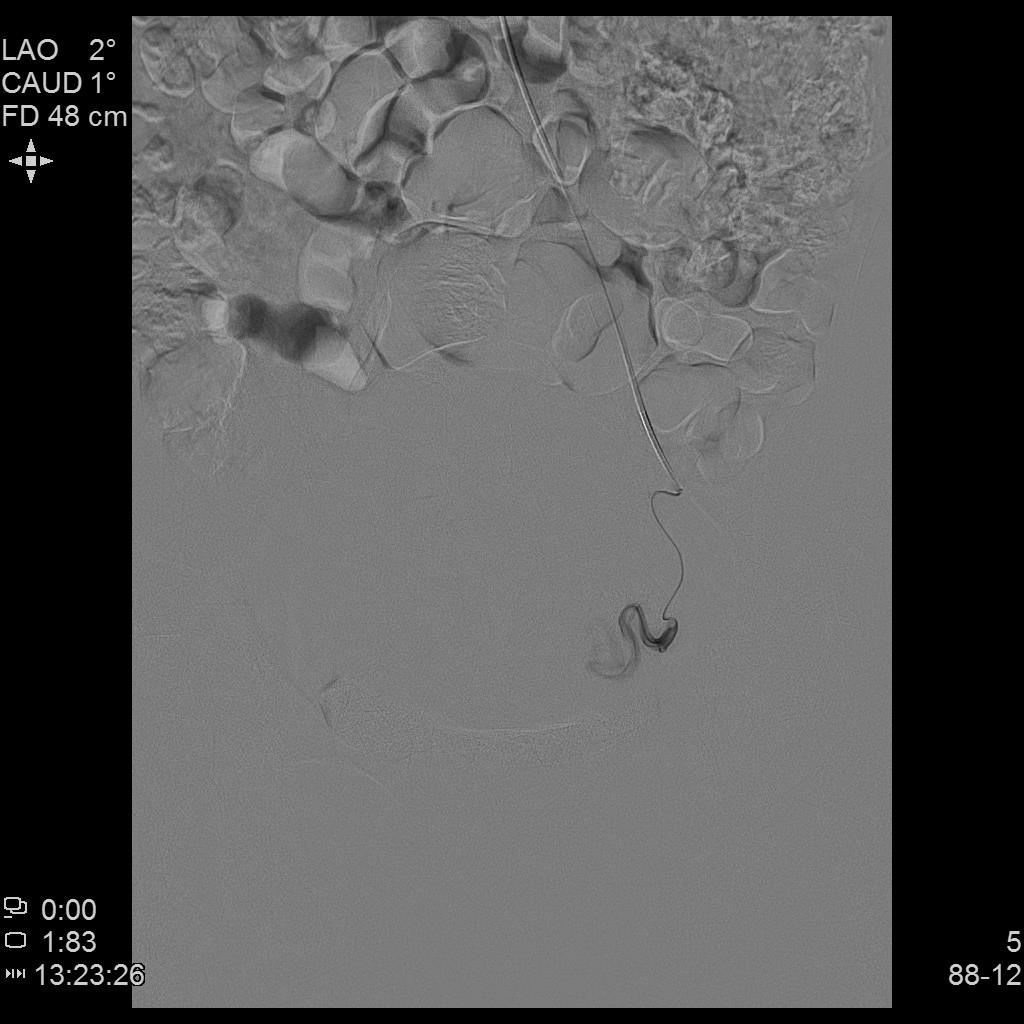

例3

中年患者,发现“子宫腺肌症”10年余,近5年痛经、月经量增多等症状明显加重,导致贫血,严重影响生活质量。

- 术前彩超、磁共振检查显示子宫明显增大,子宫前壁可见弥漫型子宫腺肌症病灶,合并粘膜下、肌壁间子宫肌瘤。

左侧子宫造影